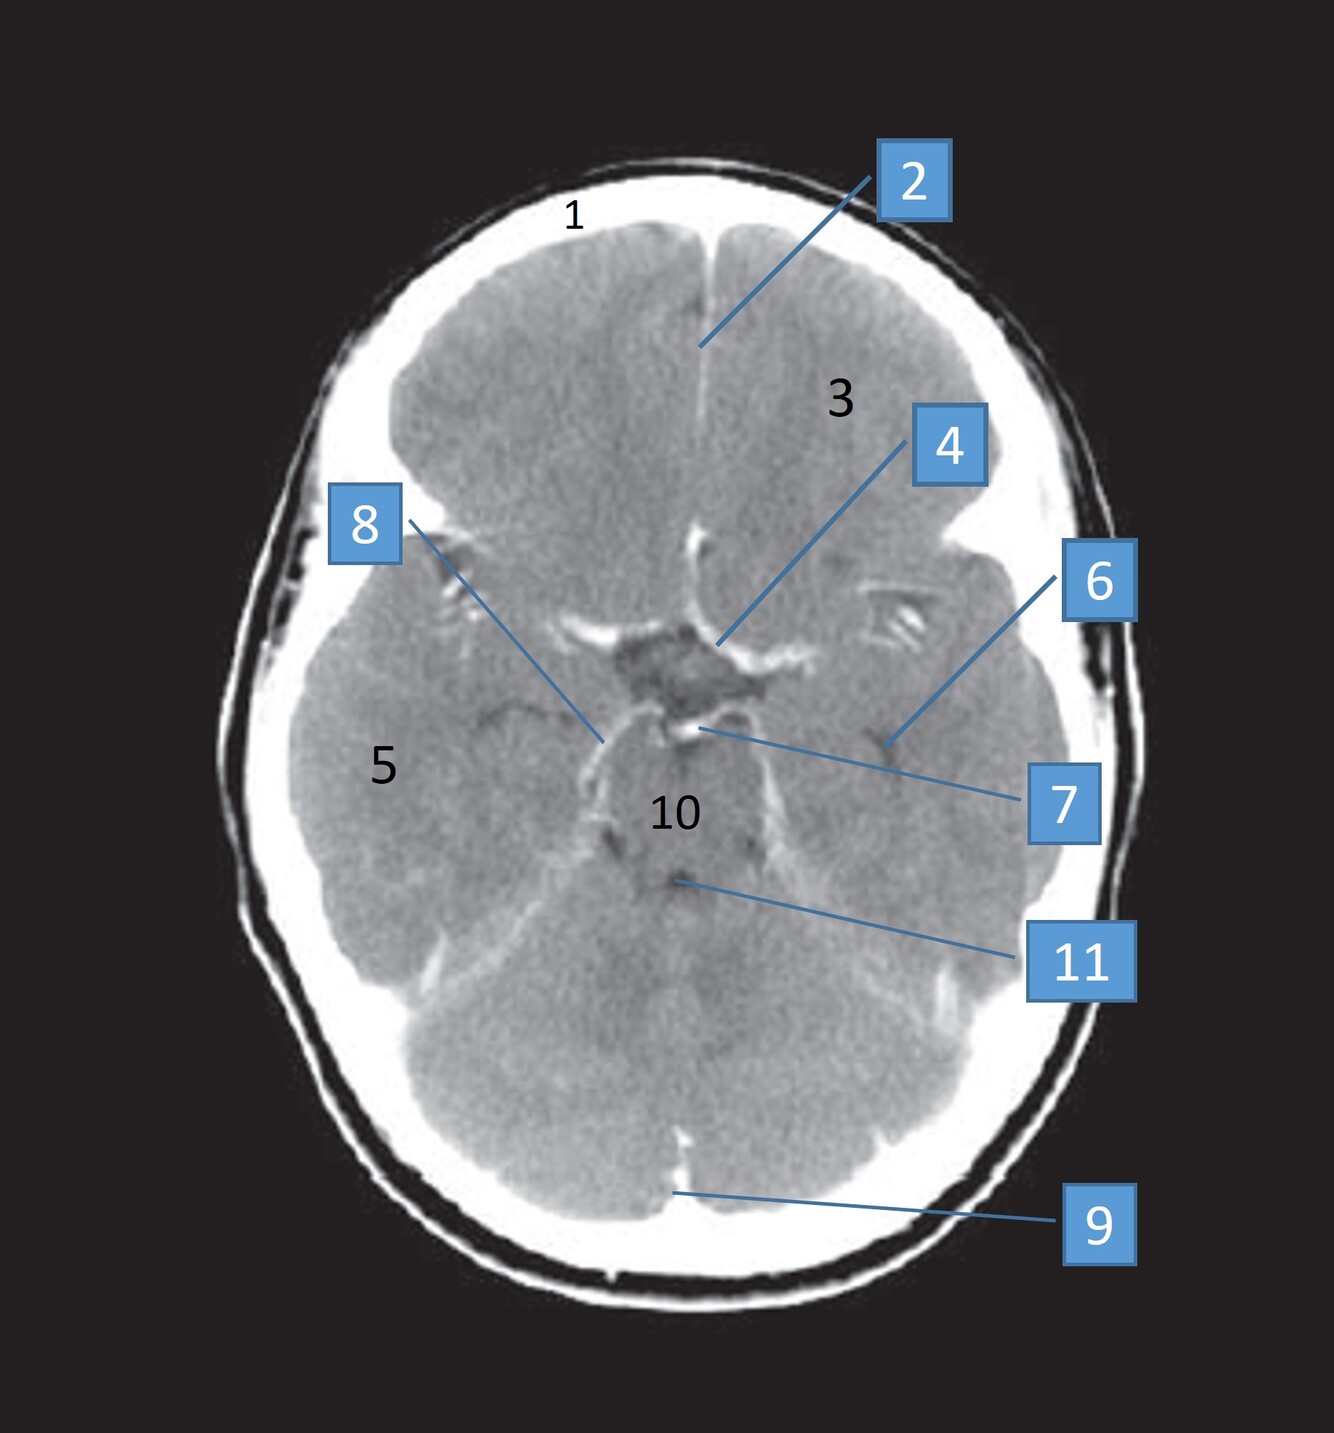

4

Label 1-6

A

1. Rt lateral ventricle

2. Lt caudate nucleus

3. Lt putamen

4. Lt globus pallidus

5. Rt temporal lobe

6. Rt Sylvian fissure

5

Label 2,3,4,5,7,8

2=Rt Caudate nucleus

3=Corpus callosum

4=Lt lateral ventricle

5=Third ventricle

7= Septum Pellucidum

8= Rt Interventricular foramen

7

Label 1-4

1. Head of Caudate nucleus

2. Lateral ventricle

3. Thalamus

4. Cerebellum

8

Label 1-5

1. Vermis of cerebellum

2. Basilar artery

3. Rt globe of eye

4. Lt temporal lobe

5. Pons